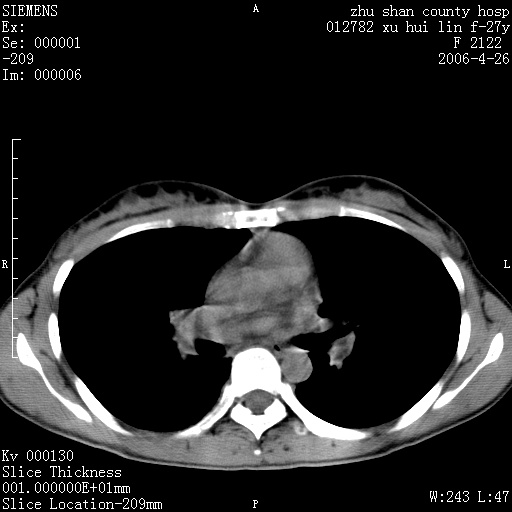

女性 病人 27岁!本院职工家属,五月前因感冒透视发现病变,ct示:左肺下叶背段感染性病变。经过半月规范抗生素治疗后复查病变无明显变化,后行四月规范抗痨治疗,复查无明显变化,后复查无效!请大家帮忙看看!

右肺下叶背段见片状高密度区,边界不清,密度不均,无钙化及空洞影,背段支气管通畅。所见层面肺门及纵隔内未见明显肿大淋巴结影。

女性 病人 27岁!本院职工家属,五月前因感冒透视发现病变,ct示:左肺下叶背段感染性病变。经过半月规范抗生素治疗后复查病变无明显变化,后行四月规范抗痨治疗,复查无明显变化,后复查无效!

诊断:首先还是考虑为慢性炎症。

结核虽然好发于下叶背段,但周围无明显卫星灶,化验结果怎样?